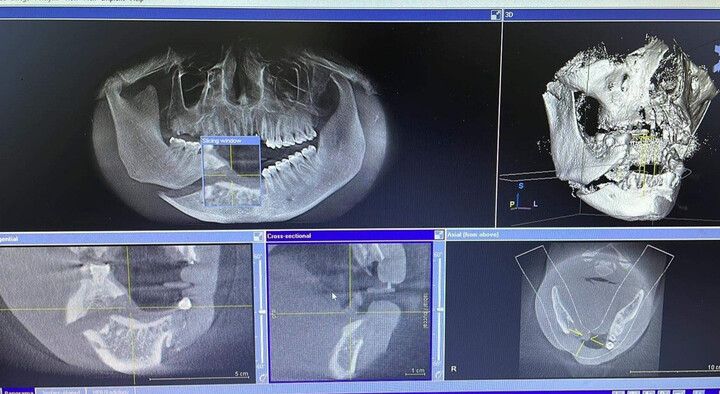

Hình ảnh chụp cho thấy nam bệnh nhân 32 tuổi mất toàn bộ răng cửa trên và dưới sau vụ tai nạn hi hữu. (Ảnh: BSCC)